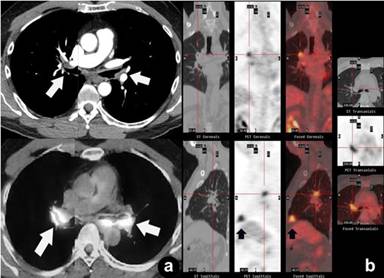

A 57-year-old white female was referred to our center for recurrent systemic IgG4-related sclerosing disease. She complained of right posterior pleuritic chest pain for 3 weeks. Three years prior to her present illness, the patient noticed that her right eyelid was drooping. PET demonstrated bilateral retro-orbital hypermetabolic lesions (Figure 12). She underwent a complete retro-orbital tumor resection of the right eye. Immunostaining of the lesion was consistent with IgG4-related sclerosing disease. After surgery, no steroid was initiated and she was asymptomatic. One year later, the patient had recurrent bouts of pneumonia. CT of the chest revealed a right lung mass (7.8x6.3 cm). Bronchoscopy was negative for malignant cells. According to the patient, CT-guided biopsy was “positive for cancer” (we were unable to obtain the official pathology report). PET showed a mass of intense tracer uptake in the right lower lung extending to the pleura (Figure 13). As a result, she underwent right middle lobe/lower lobe lobectomy. Again, immunostaining of the lung mass was consistent with systemic IgG4-related sclerosing disease. The patient was not on any postoperative cortico- or chemo-therapy and was asymptomatic for 5 months. She then became dyspneic and complained of right posterior pleuritic chest pain; a repeat radiographic imaging revealed recurrent IgG4-related sclerosing disease. She was placed on prednisone 40 mg daily, which was tapered off over a two-month period. Her symptoms were fairly controlled for another 5 months. However, she was referred to our center for recurrent symptoms secondary to uncontrolled systemic IgG4-related sclerosing disease. At our center, IgG, IgG4, IgE levels were normal (IgG: 844 mg/dL; IgG4: 28.3 mg/dL; IgE: 61.3 KU/L). These labs were not performed by the outside center. Because of similarity between systemic IgG4-related sclerosing disease and multiple myeloma due to plasma cell proliferation, she was treated with 4 cycles of a chemotherapy regimen, CyBor-D (cyclophosphamide, bortezomib, and dexamethasone). Clinical improvement was observed after the third cycle. After 4 cycles of CyBor-D, she remained asymptomatic.

Figure 13. Coronal fused PET/CT images show extensive right lower lung and pleura hypermetabolic lesions (circle). Case#3. |

Several different pulmonary patterns in patients with systemic IgG4-related sclerosing disease have been reported. These are interstitial/nodular infiltration, bronchial/interlobular wall thickening, and inflammatory pseudotumor [29, 30, 31, 32]. A study reported 9 cases of IgG4-related lung pseudotumors [30]. Similar to our Case #3, Zen et al. observed that 7 out of 9 pseudotumors located adjacent to pleura [30]; PET was only performed in Case #7 and it showed an intense tracer uptake by the pseudotumor as seen in our Case #3 (Figure 13). Eight out of 9 patients underwent either partial resections or lobectomies. Whether or not lung cancer was the preoperative diagnosis in these 8 patients was unclear. Only one patient (Case #9) did not undergo surgery and correctly diagnosed by transbronchial lung biopsy. For this case, after one month of corticosteroid treatment, the pseudotumor size was markedly decreased, and the patient’s symptomatology (hemoptysis) resolved. In our Case #3, the patient would have spared from lobectomy if she was diagnosed with systemic IgG4-related sclerosing disease preoperatively. As demonstrated in Figures 12 and 13, PET/CT imaging should be considered prior to any surgical resection in patients with a history of IgG4-related sclerosing disease because it helps to reach the correct diagnosis by targeting biopsy sites.